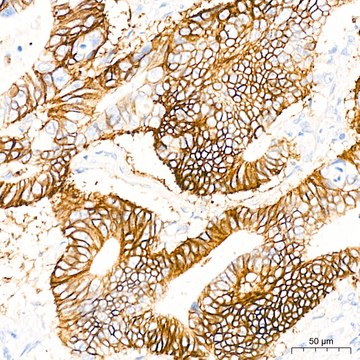

Anti-GRIK2 Antibody, clone 4B4L9, Rabbit Monoclonal

IHC, WB

immunohistochemistry: 1:50 - 1:200, western blot: 1:500 - 1:2000

General description

A synthetic peptide corresponding to a sequence within amino acids 50-150 of human GRIK2 (Q13002).